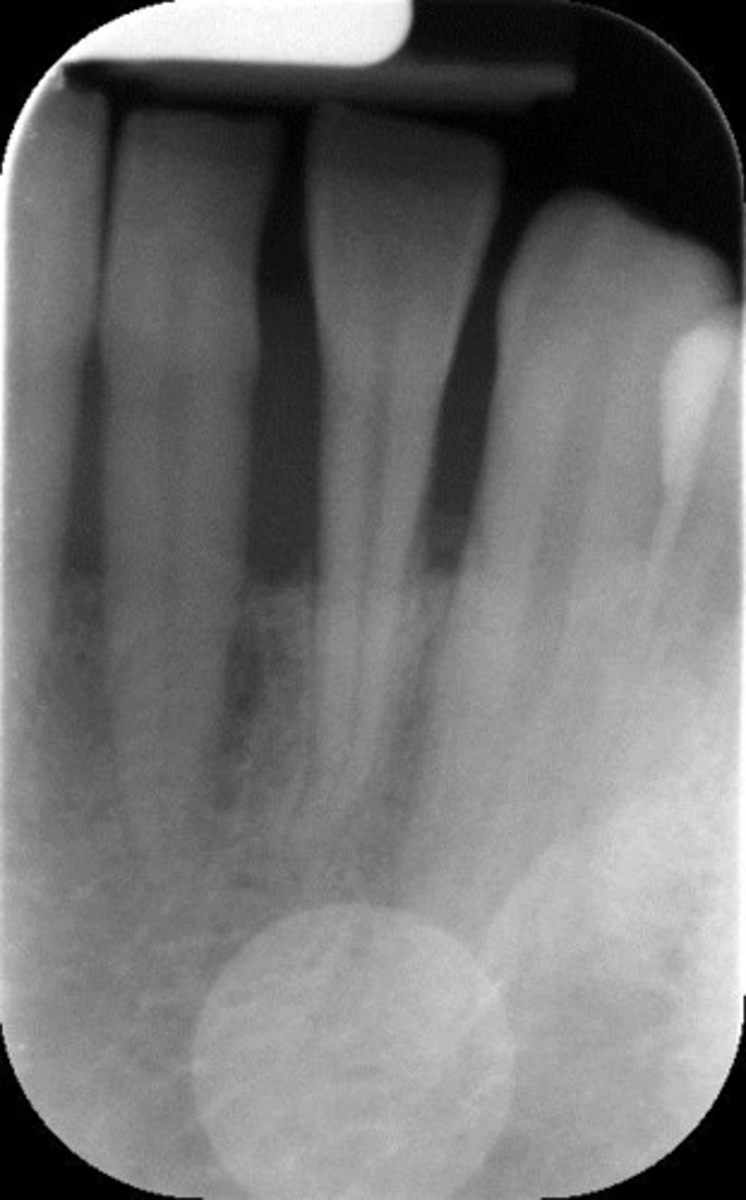

Elongated, vertical angulation, film holder (metal bar)

What is this error?